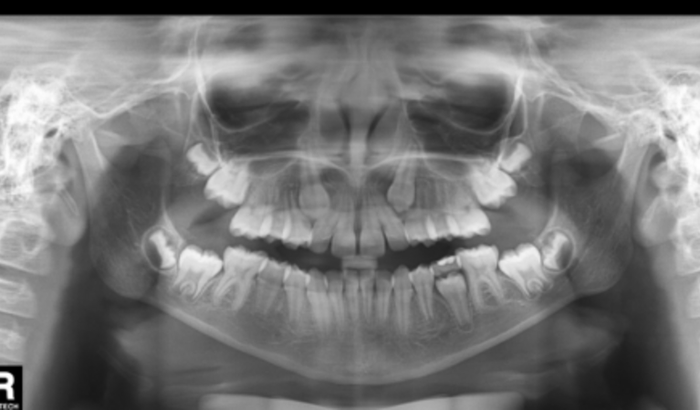

Olá! Sou Eloá, recentemente fui diagnosticada com uma má formação na parte superior da mandíbula. Tenho que fazer inicialmente 08 seções com um especialista numa cidade a 220km da minha, com media de gasto em torno de 600,00 a 700,00 com deslocamento e consultas. Situação esta que tem possibilidade de cirurgia, que esperamos que não aconteça.